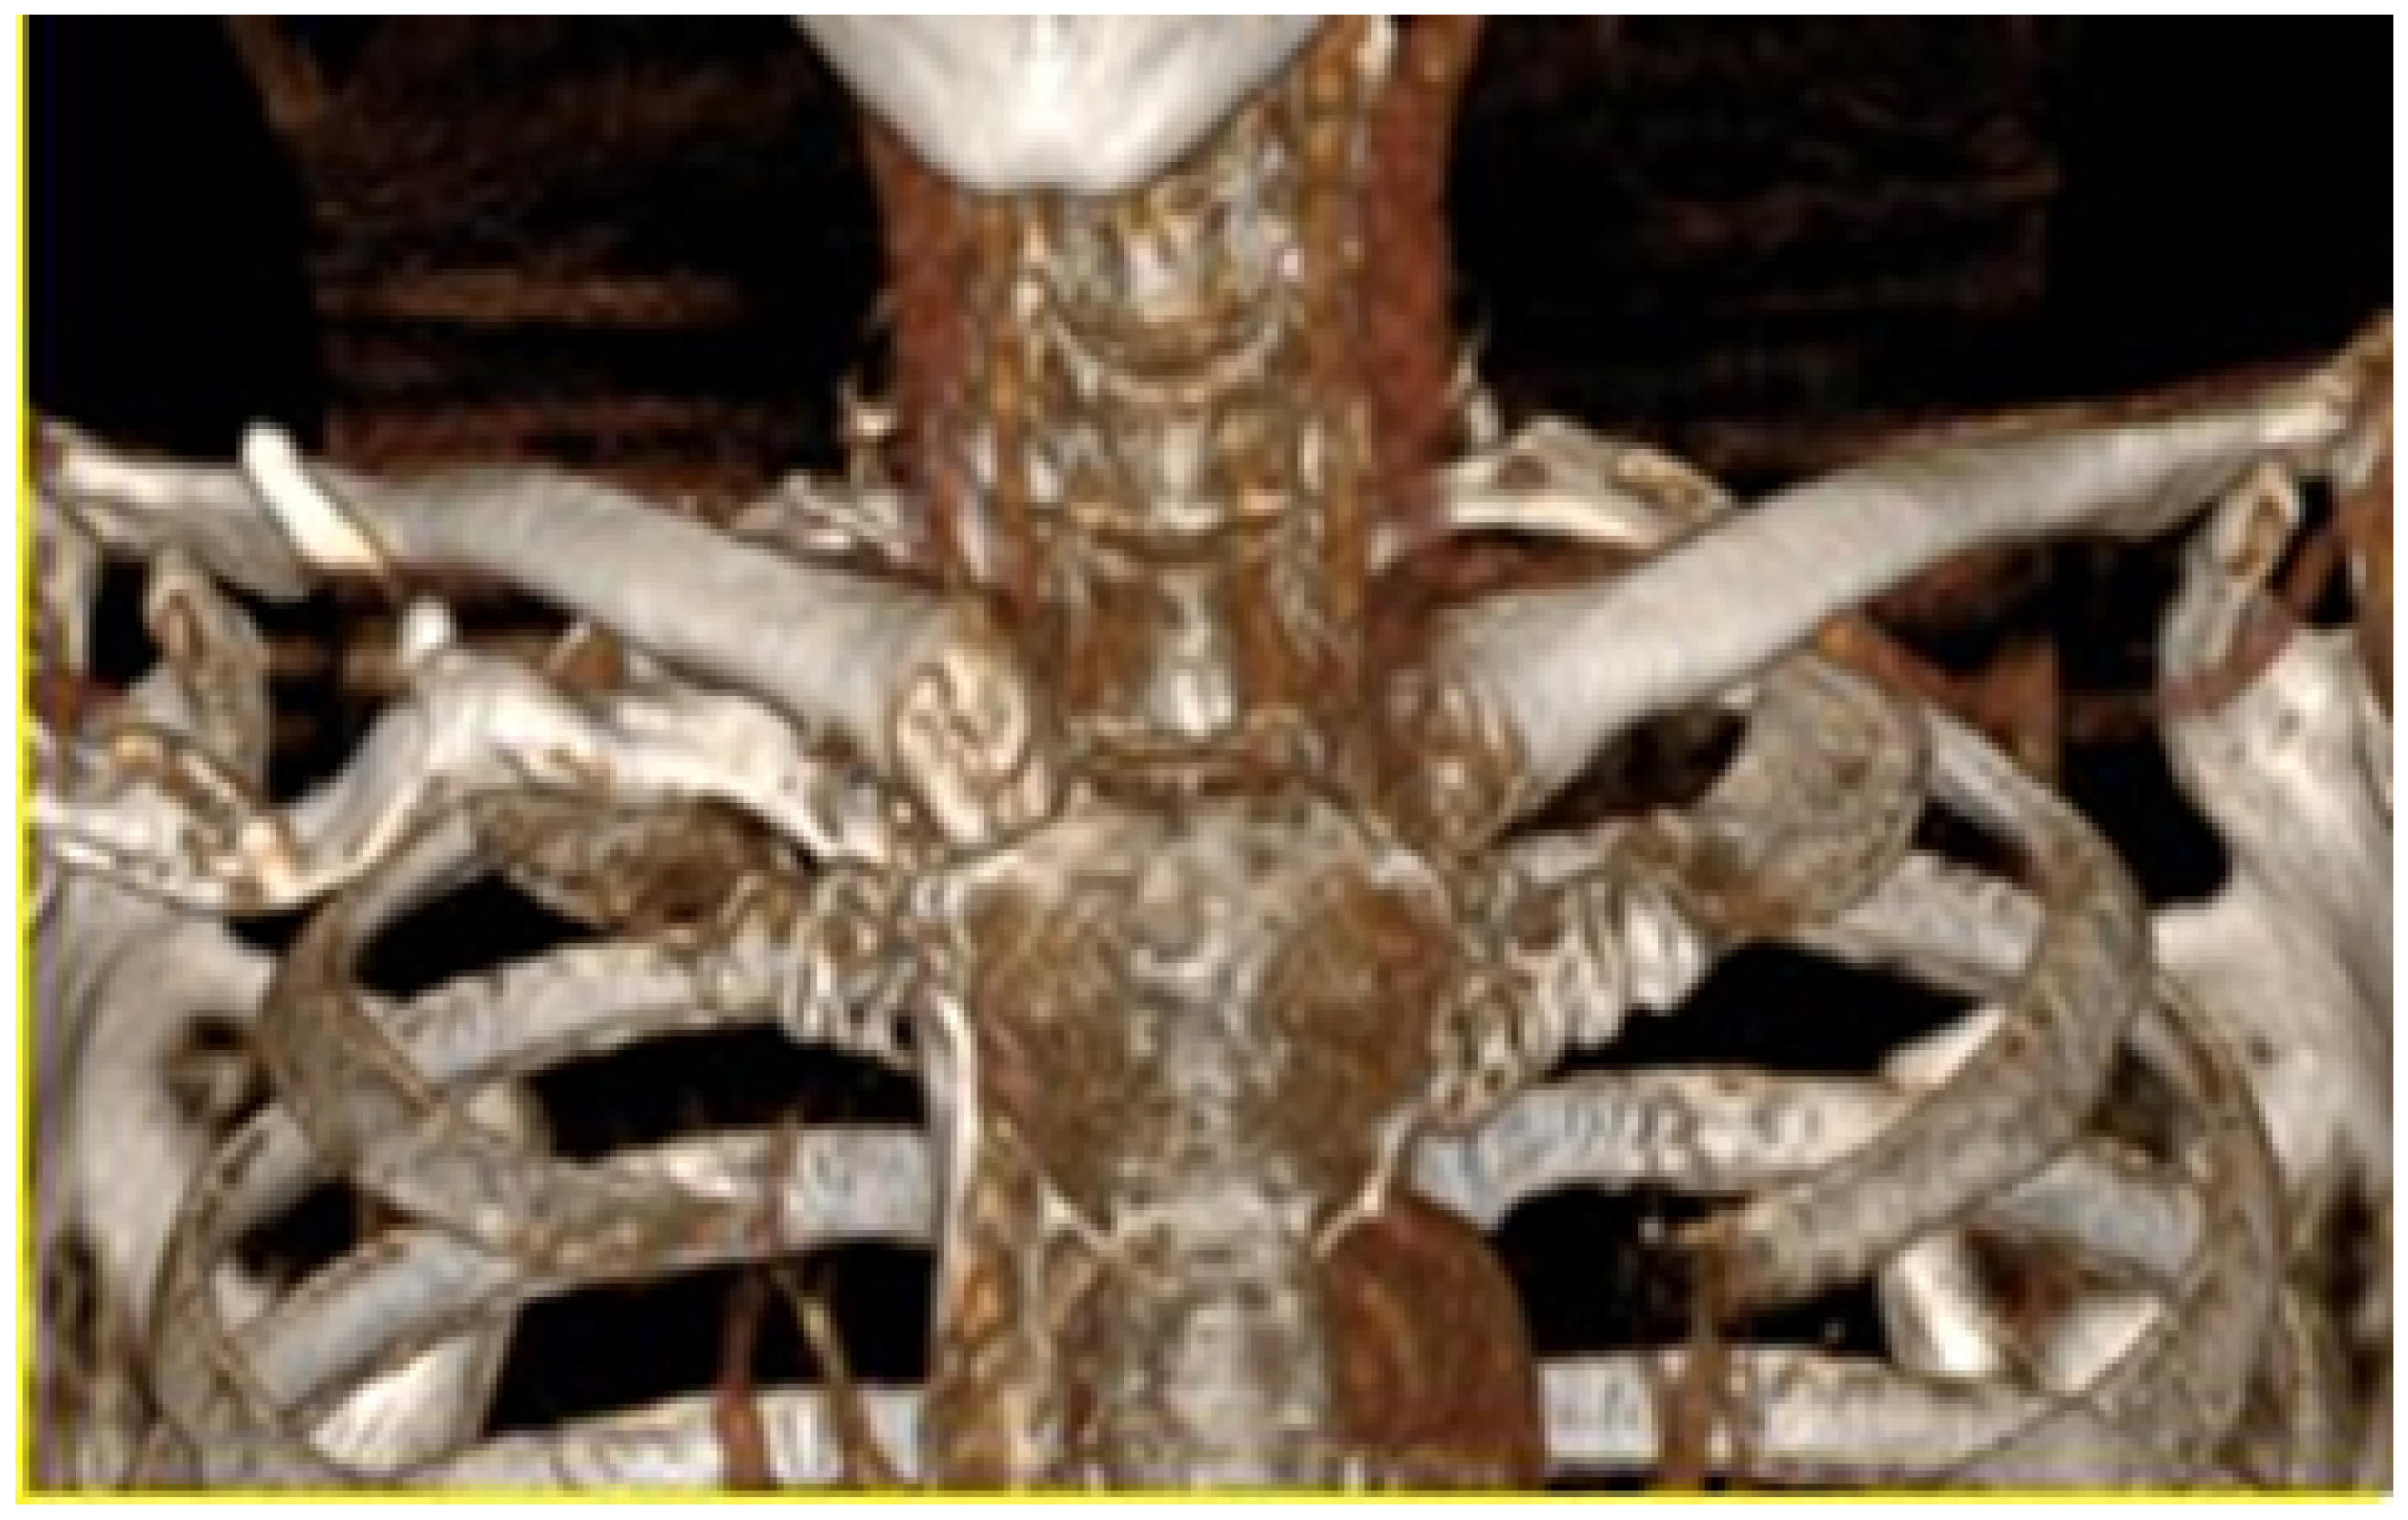

3.6. Case 6: Right Sternoclavicular Tumour

A 55-year-old female patient was diagnosed with a tumour in the right sternoclavicular region, which compromised half of the sternal handle and the proximal third of the clavicle on the same side. As in the preceding cases, the three-dimensional digital model of the entire area was obtained from the tomographic images of the affected area. Figure 38 shows the process of delimiting the damaged bone structure.

3.6.2. Surgical Planning

Figure 38. Isolation of the clavicular tumour (left). Clavicle and sternum reconstruction model (right).

Figure 39. Bone segmentation model and anatomical reconstruction (left). Anatomical positioning of the cutting guide (right).